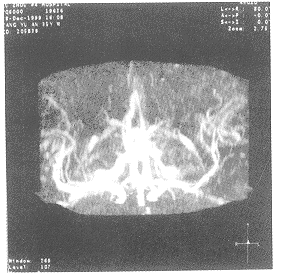

图1

图2

图3

图1、2、3箭号所指为变细的大脑中动脉及其供血工内减少的血管网